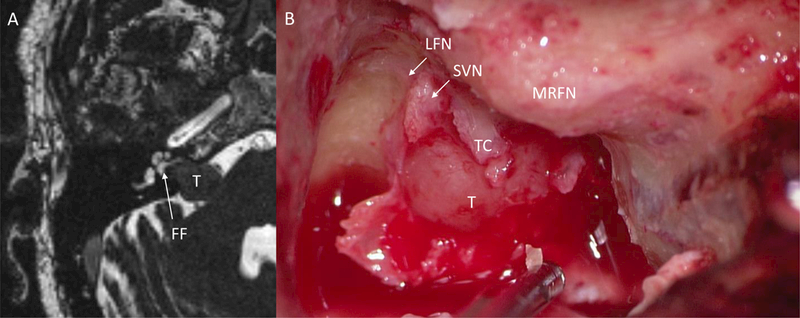

Translabyrinthine resection of VS offers an ideal opportunity to examine the anatomic relationships in the lateral IAC by allowing its full decompression and exposure. Interestingly, even in tumors with a sizeable fund fluid cap on preoperative MRI, intraoperative examination revealed tumor extending to the IAC fundus without any visible fundal fluid cap in the tumors in this series (Fig. 3).

Figure 3.

Comparison of pre-operative MRI with intraoperative findings. A) Pre-operative CISS MRI demonstrating a fundal fluid cap (white arrow) in the lateral IAC from the lateral aspect of the tumor to the cochlea aperture. B) Intraoperative photograph during a translabyrinthine approach showing tumor filling the fundus with tumor spanning the transverse crest. Fundal fluid was absent on intraoperative examination. T, tumor; FF, fundal fluid; LFN, labyrinthine facial nerve; SVN, superior vestibular nerve; MRFN, mastoid ridge facial nerve; TC, transverse crest